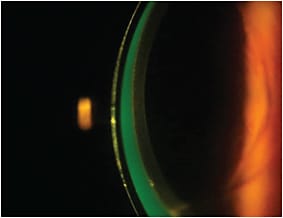

Lens Fitting and Follow-up Care The patient’s left eye was diagnostically fit with a 16mm Europa (Visionary Optics) scleral contact lens with parameters of 52.00D base curve radius (BCR) and –6.00D power. The patient’s vision OS at the dispensing visit was 20/25. The scleral lens had complete central corneal clearance and fit without excessive compression (Figures 2, 3, and 4). (Click here to view a video of an optic section assessment showing acceptable clearance of a scleral lens courtesy of Dr. DeNaeyer.)

Figure 4. An optic section reveals good apical clearance for the left scleral lens in Case #1.